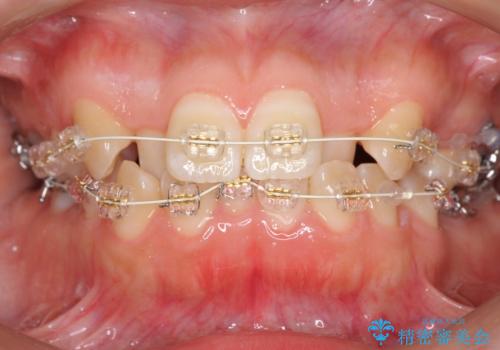

よくある悩み 前歯が裏に2本入っているのを治したい

- 前歯が2本裏に入ってしまっているのを治したいとのことでした。

プラン1:上の正中をずらさない・・・上下左右4本抜歯

プラン2:上の正中は少し左にずれる・・・左の上下2本抜歯

を提案し、プラン2を選択されました。

最小限の抜歯により矯正ができたと、喜んでいただきました。